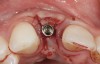

The crown and screw-retained custom abutment were removed, and a surgical cover screw was placed into the implant, thereby allowing spontaneous gingival augmentation in situ (Figure 33 and Figure 34). Note that the lingual aspect of the implant site was significantly more coronal than the labial aspect, which was positive because the defect would be limited to a facial–lingual defect. A fixed RBR bridge was cemented on the adjacent teeth and used as a tooth-supported transitional provisional restoration (Figure 35). A few weeks were allotted to let the soft tissue heal and migrate around the cover screw (Figure 36) to see if there would be complete coverage, thereby allowing a soft-tissue augmentation procedure to be performed with primary flap closure as in clinical scenario No. 2. The major obstacle in achieving a positive tissue response was that the implant depth was also deficient because the implant–abutment connection was at the level of the free gingival margin. It was decided that the best treatment option would be to remove the implant. A high-powered reverse-torque device (Fixture Remover Kit, NeoBiotech, www.neobiotechus.com) was used to remove the implant atraumatically (Figure 38 through Figure 41). The implant socket was allowed to heal for several months not unlike an extracted tooth (Figure 42). A new implant was placed in a better position from both a restorative and esthetic perspective (Figure 43), and after a few months of healing, a new crown was made (Figure 44). A satisfactory functional and esthetic result was achieved (Figure 45 and Figure 46) without employing pink porcelain.

Fig 32. A dissatisfied patient presented with significant midfacial recession of implant restoration of tooth No. 26. Pink ceramic material was used unsuccessfully to prosthodontically compensate for the lost midfacial tissue.

Figure 32

Fig 33. Excessive facial angulation of the implant placement shown with an abutment driver in the access screw hole.

Figure 33

Fig 34. A surgical cover screw was placed in an attempt to decoronate the implant and gain soft-tissue coverage in situ.

Figure 34